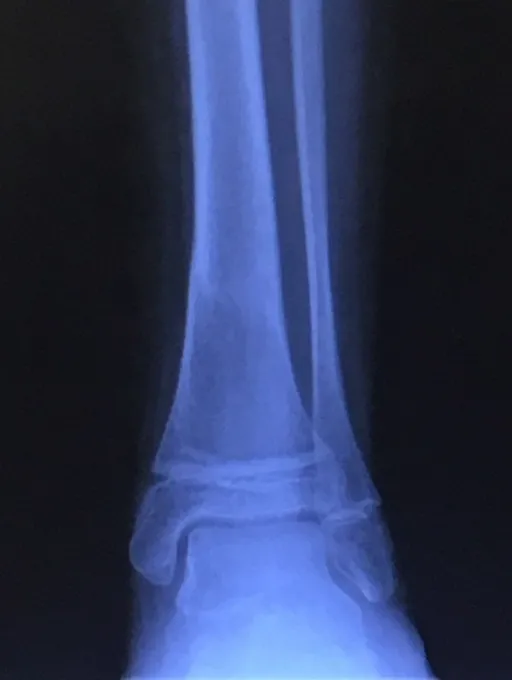

Below, Tibia and Fibula Fracture in a 16-year-old injured skiing. The patient presented to the office 8 days after injury with a displaced fracture. The first 2 films show the displacement in the fracture of the tibia. After an above knee cast is applied, the cast is wedged under fluoroscopy and new xrays show the near perfect reduction of the fracture. The white arrows show the area where the cast is wedged

Xray of Tibia Fracture